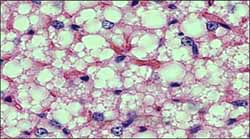

De acuerdo a sus características, el tejido adiposo se clasifica en unilocular o tejido adiposo blanco o claro –más corriente en los adultos- y multilocular, o grasa parda (Figura 1). La grasa parda –que sólo se ve en mamíferos- es el único tejido en el cual se puede demostrar fácilmente el desacoplamiento de la fosforilación oxidativa como mecanismo termogénico.

Las células del primer tipo son poliédricas -de 50 y 150 micras de diámetro y se ven como un pequeño anillo de citoplasma rodeando una vacuola que contiene una sola gota de lípido que desplaza las organelas hacia la periferia, además de un núcleo excéntrico y aplanado.

El tejido adiposo multi-locular o grasa parda tiene células poligonales y más pequeñas que las del tejido adiposo blanco, su citoplasma contiene numerosas gotas de lípido de diferente tamaño y numerosas mitocondrias con abundantes crestas; su núcleo es central y esférico. Este tejido graso se asocia con numerosos capilares sanguíneos.